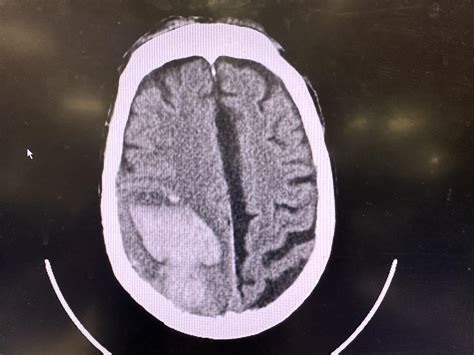

Physicians rely heavily on neuroimaging to diagnose and quantify a midline shift. The severity is typically measured in millimeters, indicating how far the brain structures have moved from the central axis. A greater shift generally correlates with a poorer prognosis and requires more urgent surgical or medical management.

CT Scan Typically the first line of defense; excellent for identifying acute blood, bone fractures, and rapid structural changes.

⚠️ Note: Measuring the degree of shift on imaging is crucial for clinical decision-making. A shift of 5mm or more is often categorized as significant and frequently requires surgical intervention.